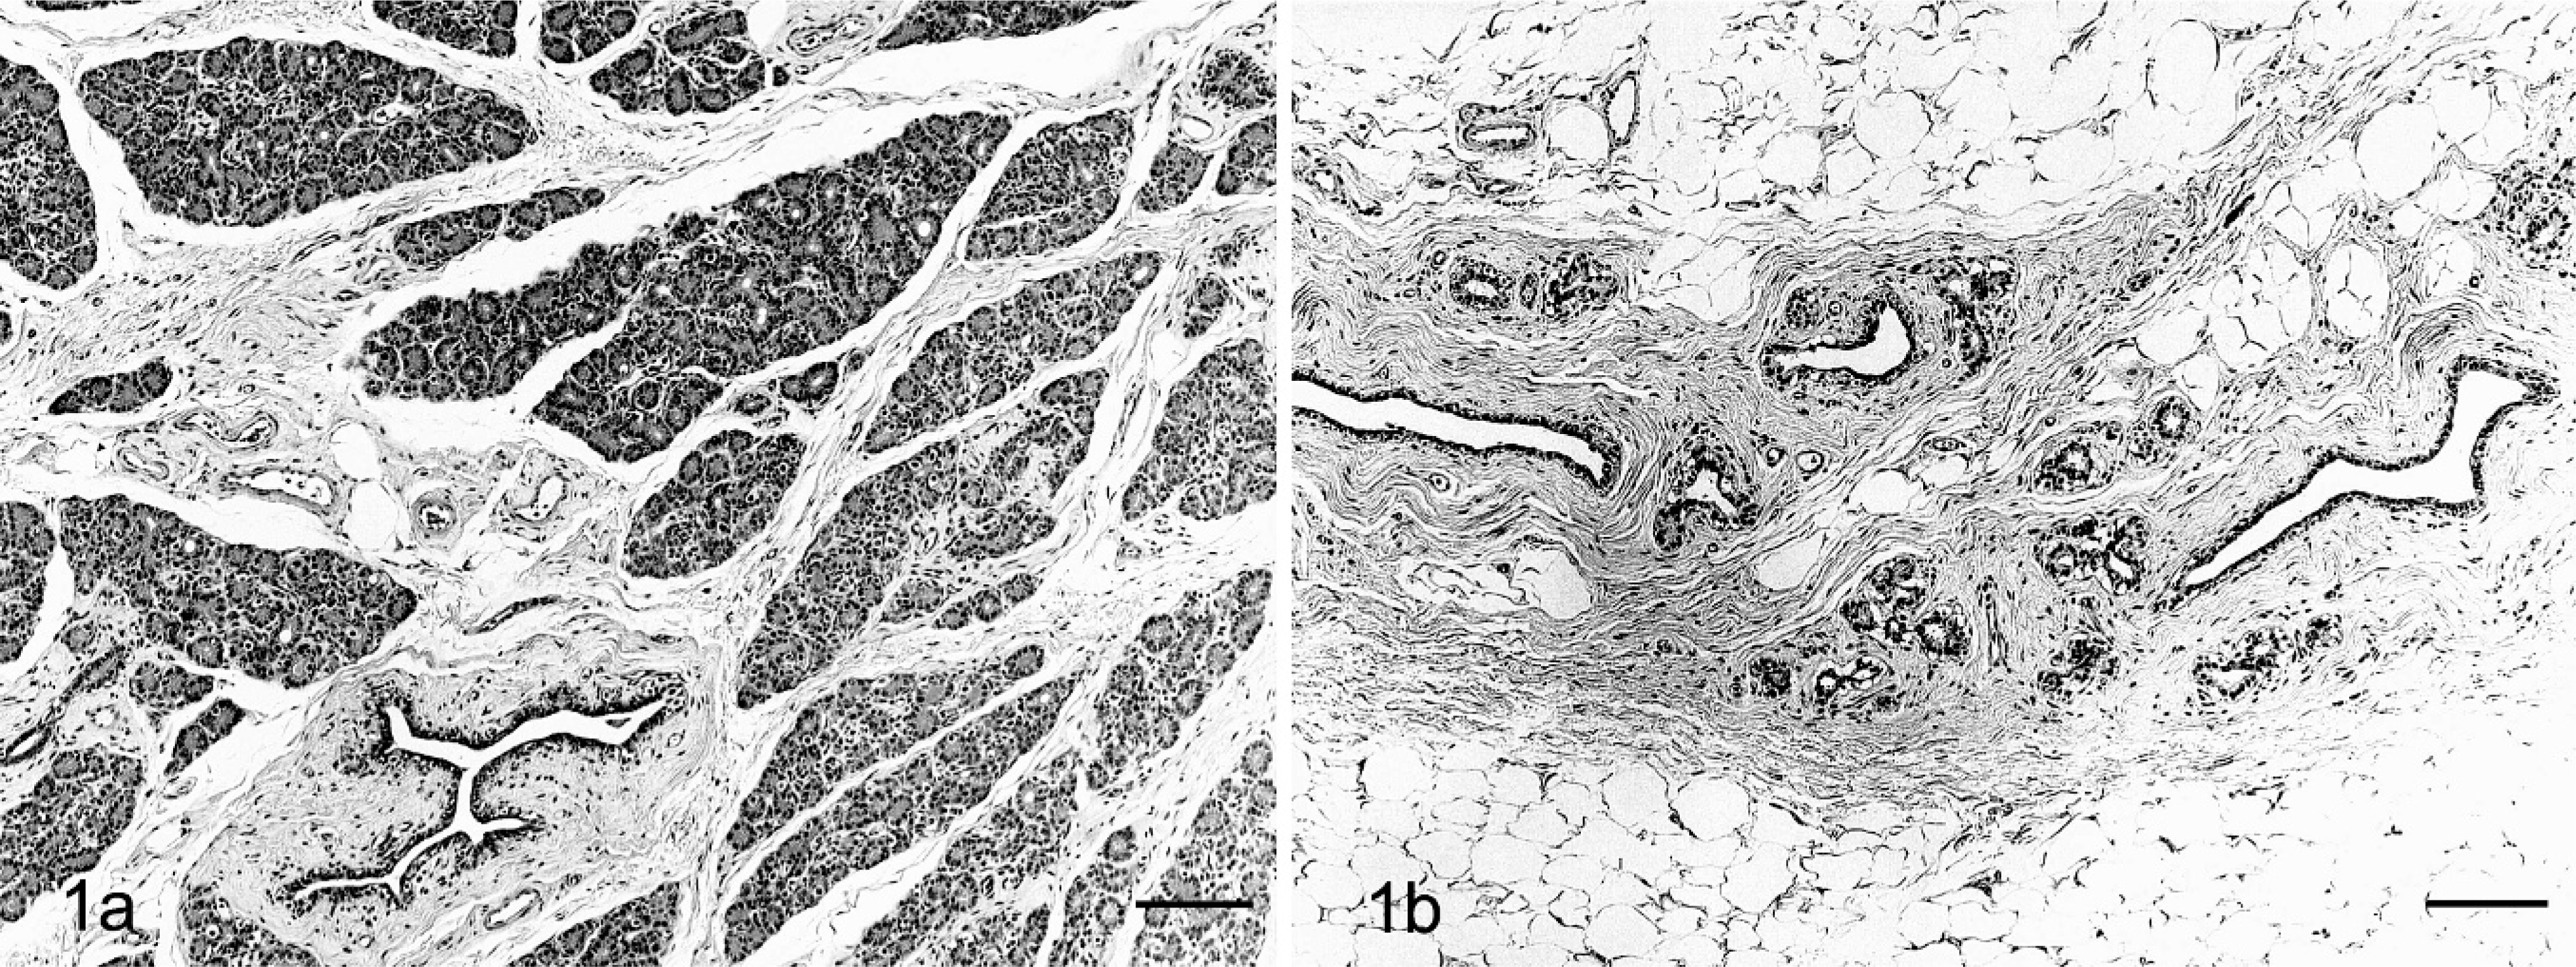

Mammary glands. HE. Bars = 200 µm. Fig. 1a. Sham monkey. No abnormal changes are seen. Fig. 1b. OVX monkey. Atrophy of mammary glands is seen; the cellularity and number of lobules are decreased, but the main duct is preserved; supporting connective tissue is decreased, and the stroma is replaced by adipose tissue.

In normal human-breast tissue, parenchymal changes during and after menopause reflect hormonal alterations in which serum estrogen and progesterone levels decline, although androgen levels, largely testosterone, are not diminished. As early postmenopausal atrophy of the human breast, general loss of acini with focal hyalinization of intralobular stroma is seen. 7 As postmenopausal involution progresses, the epithelial component completely atrophies and lobules become entirely hyalinized, forming hyaline nodules (ghost lobule). 7 The breast stroma also undergoes involutional changes in which alterations occur in elastic and collagen fibers, resulting in loss of supporting connective tissue, whereas adipose tissue increases. 7 The present study confirms that structural alterations in the mammary glands of OVX monkeys were very similar to early postmenopausal atrophy of the human breast.